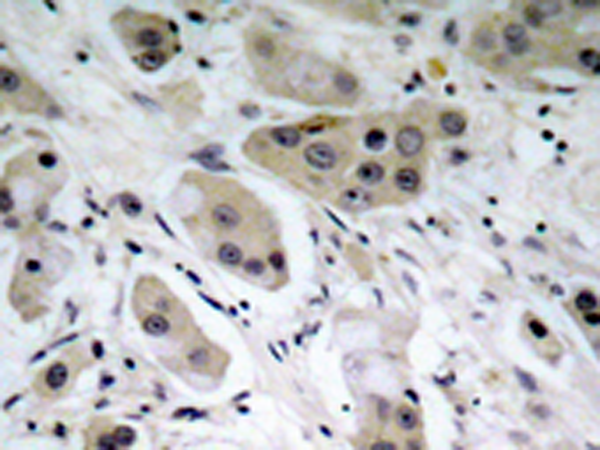

IHC positive control: |

Human breast carcinoma |

IHC Recommend dilution: |

50-100 |